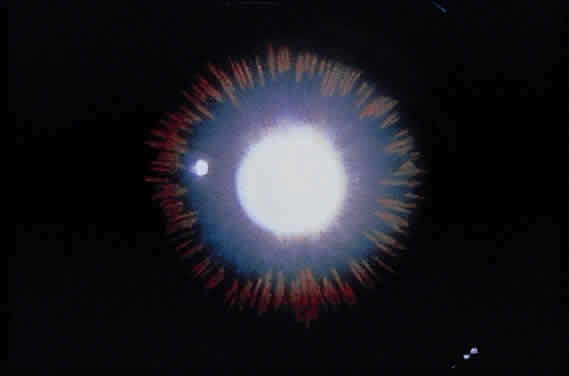

Exfoliative material frequently is observed at the pupillary border (Fig. 4) and should suggest the diagnosis of exfoliation even before the pupil is dilated.27 In addition, defects of the pigmented pupillary ruff are commonly seen. Aasved reports pupillary defects in 6.1% of eyes without XFS and in 74% of eyes with XFS.50 He further notes that in patients with unilateral XFS, pupillary ruff defects were twice as common in the affected eyes when compared with the fellow eyes. Iris transillumination defects in a moth-eaten pattern often are observed. Although these generally are limited to the region of the sphincter (Fig. 5), several patients also have diffuse midperipheral defects.51

Fig. 5. Moth-eaten pattern of peripupillary iris transillumination defects seen in exfoliation syndrome.